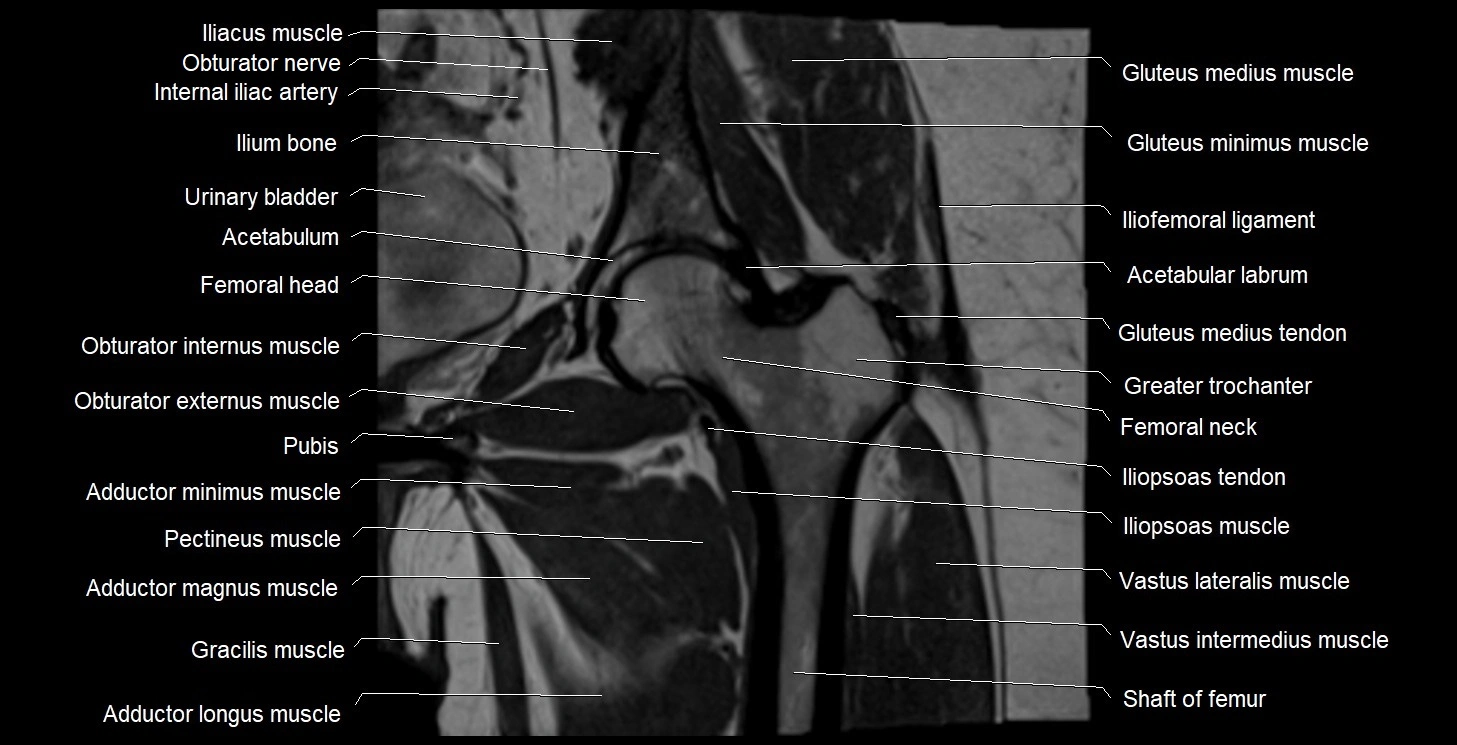

- Acetabulum

- Gluteus medius muscle

- Gluteus minimus muscle

- Gracilis muscle

- Greater trochanter

- Head of femur

- Iliofemoral ligament

- Iliopsoas muscle

- Iliopsoas tendon

- Ilium bone

- Inferior pubic ramus

- Internal iliac artery

- Lesser trochanter

- Neck of femur

- Obturator externus muscle

- Obturator internus muscle

- Obturator nerve

- Pectineus muscle

- Pubic bone

- Urinary bladder

- Vastus intermedius muscle

- Vastus lateralis muscle